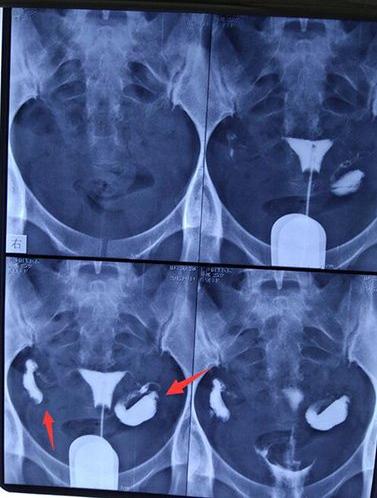

做子宫造影有哪些注意事项

做输卵管造影要多少钱?专家解读造影费用

做造影对身体的危害有哪些呢什么是子宫输卵管造影

但都没有怀孕.第三个月自己决定做造影.

什么情况下需要做输卵管造影

什么情况需要做输卵管造影

跟大家分享一下我的输卵管造影经历

哪些人需要做输卵管造影?

姐妹们没有怀上,一定做个造影看看输卵管是否畅通.

4步讲解输卵管造影检查过程

输卵管造影不要随便做输卵管造影注意事项

输卵管造影2月19日做的造影2月20

备孕检查做输卵管造影疼吗影响输卵管造影疼痛的因素

你好,我做造影检查左侧输卵管梗阴,右侧

不孕,做了造影疑似宫腔粘连了帮忙看下

输卵管造影很疼吗?是怎么做的?

做输卵管造影前后,该需要注意什么?

做个输卵管造影能检查还能治疗?它有什么神奇之处?

输卵管造影检查注意事项

做输卵造影要做什么检查

超生输卵管造影费用图片合集